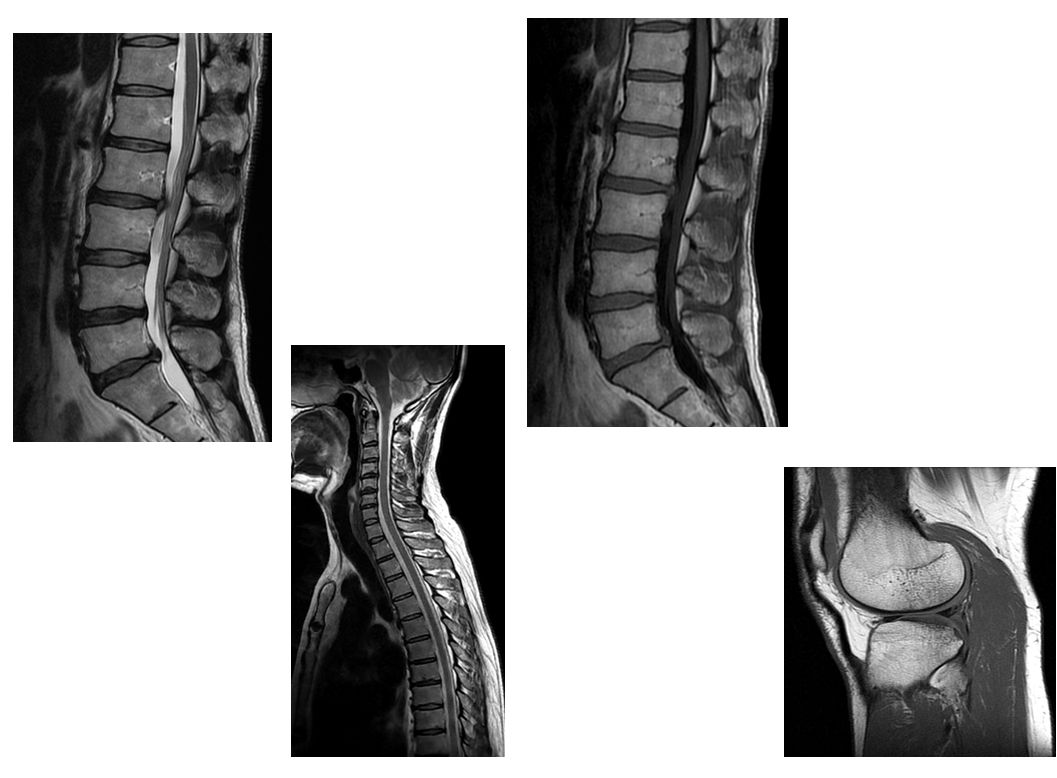

MRI装置